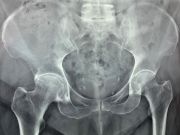

2. Intracapsular fracture of the right hip in a 74-year-old female.

Treatment: Total hip arthroplasty

I. Anteroposterior x-ray pelvis shows the fracture on the right hip II. Anteroposterior x-ray pelvis shows the total hip arthroplasty three months down the line from the operation III. Lateral view hip shows the total hip arthroplasty three months down the line from the surgery